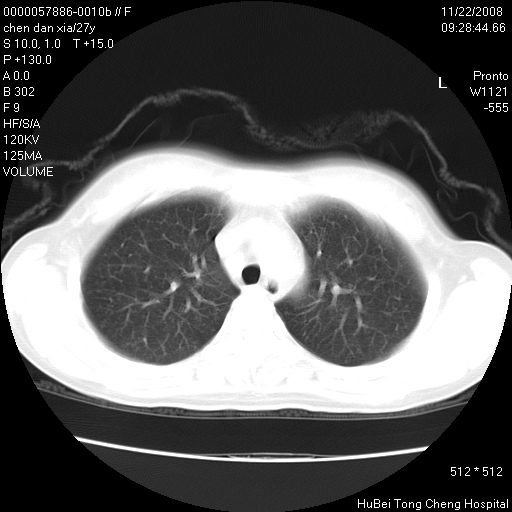

标题: CT16752:F,27Y。发热咳嗽20余天,伴盗汗。 [打印本页]

标题: CT16752:F,27Y。发热咳嗽20余天,伴盗汗。

考虑双肺粟粒性肺tb,右侧胸膜增厚.

气管前腔静脉后淋巴结肿大 右肺门纹理模糊

淋巴结核?

右下肺见片絮状影,两肺野内分布不均的小结节影,结核并肺内播散可能性大,建议结合实验室检查 .

右下肺纹理模糊;纵隔可见肿大淋巴节;右心缘旁结节,边缘光滑,纵隔窗病变范围较肺窗明显小,首先考虑右下肺结核,不排外淋巴瘤

双肺纹影普多,部分呈网状,支炎或淋巴管炎?

纵隔内淋结肿

局部胸膜增厚

下肺结节,结节内钙化,肺门纵隔淋巴肿大 结核可能性大

似有粟米状结节。考虑粟粒型肺结核?

1)考虑两肺感染性病变。2)纵隔淋巴结肿大。